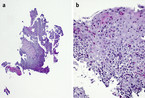

Bei der Aufnahmeuntersuchung gibt der Patient an, keinerlei Nahrung oder Flüssigkeit herunterschlucken zu können, selbst Speichel wird ausgespuckt. Der körperliche Untersuchungsbefund ist unauffällig, insbesondere ist keine Struma palpabel und es zeigt sich eine normale Larynxverschieblichkeit. Auch laborchemisch ergeben sich keine wegweisenden Befunde: Hb 11,8 g/dl, Thrombozyten 214.000/µl, Leukozyten 4.000/µl, davon 50 % Lymphozyten, 44 % segmentkernige Granulozyten, 2 % Monozyten, 4 % Eosinophile; Normwerte für Elektrolyte, Kreatinin, ALT, LDH, Harnsäure, CRP, Gerinnungsparameter und Immunglobuline. Eine Abdomensonographie zeigt einen Normalbefund, ein Ösophagus-Breischluck zeigt einen regelrechten Schluckakt, das Kontrastmittel wird nach dem zweiten Schluck jedoch wieder erbrochen. In einer flexiblen Ösophagogastroduodenoskopie mit Biopsien zeigen sich die in Abbildung 1 dargestellten Befunde.

Endoskopisch (Abb. 1) zeigt sich eine unregelmäßige Ösophagusschleimhaut mit weißlichen Auflagerungen, die nicht abstreifbar sind. Es sind eine längliche Fältelung sowie eine Ringbildung erkennbar und die Peristaltik scheint vermindert. Histologisch (Abb. 2) zeigt sich ein hyperplastisches Plattenepithel mit ausgeprägter eosinophiler Ösophagitis (mind. 50 eosinophile Granulozyten bei 40-facher Vergrößerung). Somit besteht makroskopisch und histologisch das Bild einer eosinophilen Ösophagitis (eosinophilic esophagitis, EoE).

Bei klinischem Verdacht sollte eine Ösophagogastroduodenoskopie (ÖGD) mit Biopsien durchgeführt werden (Abb. 3). Typische makroskopische Veränderungen finden sich in ca. 90 % der Fälle [4]. Mögliche Befunde sind Ringbildungen, weiße Exsudate/Plaques, Längsfurchen, ein Schleimhautödem, Strikturen und eine Fragilität der Mukosa [1, 3, 4]. Histologisch finden sich eine Eosinophilie mit > 15 Eosinophilen/high power field (HPF), eosinophile Mikroabszesse sowie unspezifische Veränderungen, wie beispielsweise eine Basalzonenhyperplasie [5]. Laborchemisch kann teilweise eine Eosinophilie im peripheren Blut gemessen werden [6], diese ist jedoch nicht immer vorhanden und lässt sich aufgrund der häufig zusätzlich bestehenden atopischen Erkrankungen nicht sicher der EoE zuordnen. Nach einer 8-wöchigen Therapie mit Protonenpumpeninhibitoren (PPI) in einer Dosierung von 1 – 2 mg/kg/Tag (maximal 40 mg/Tag) muss erneut eine ÖGD mit Biopsien erfolgen. Erst wenn hier histologisch weiter > 15 Eosinophile/HPF in der Ösophagusschleimhaut detektiert werden können, kann die Diagnose einer EoE gestellt werden. Bei einer Reduktion der Eosinophilen nach PPI-Therapie auf < 15 Eosinophile/HPF müssen andere Differenzialdiagnosen, z. B. eine PPI-responsive EoE oder eine gastroösophageale Refluxerkrankung (gastroesophageal reflux disease, GERD), in Betracht gezogen werden.

Unser Patient

Bei unserem Patienten begannen wir nach Erhalt der Befunde eine Therapie mit Omeprazol 40 mg/Tag für 8 Wochen. In einer anschließenden Re-Endoskopie zeigte sich zwar makroskopisch eine leichte Besserung der Befunde, es waren jedoch immer noch typische Veränderungen einer EoE (hier insbesondere eine Längsfurchung sowie weißliche, punktförmige Erhabenheiten und ein typisches Ablederungsphänomen bei Biopsierung aufgrund der pergamentartigen Schleimhaut) vorhanden. Auch histologisch persistierte die Eosinophilie mit > 50 eosinophilen Granulozyten/HPF in der Ösophagusschleimhaut. Wir veranlassten eine umfassende allergologische Diagnostik zur Identifikation möglicher auslösender Antigene. Weder das Gesamt-IgE noch der spezifische ImmunoCAP auf Nahrungsmittelallergene (Eiklar, Milcheiweis, Dorsch (Kabeljau), Weizenmehl, Erdnuss, Sojabohne, Haselnuss, Karotte, Sellerie) zeigten pathologische Werte.